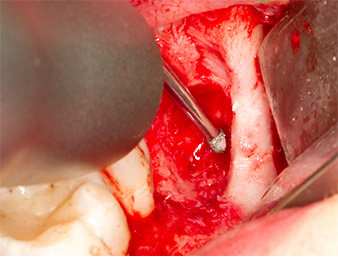

Sous bloc nerveux et anesthésie locale, le site d’intervention est ouvert et les tissus mous sont exposés afin d’accéder à la zone rétromolaire buccale (Fig. 3).

Le tissu recouvrant le reste radiculaire n’est pas entièrement ossifié et est essentiellement constitué de tissu de granulation modifié par l'inflammation (Fig. 4).